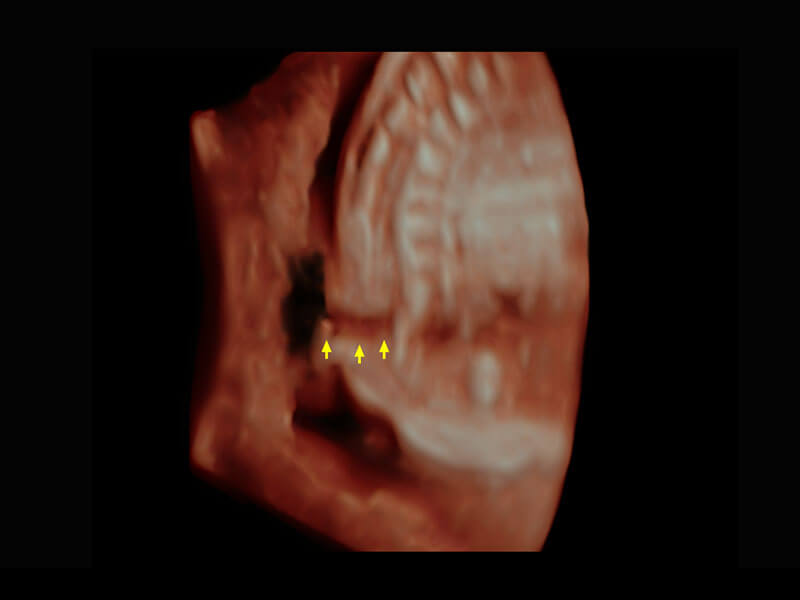

P60搭载一系列胎儿心脏成像技术,实现精细的胎儿心脏评估。

胎心容积成像